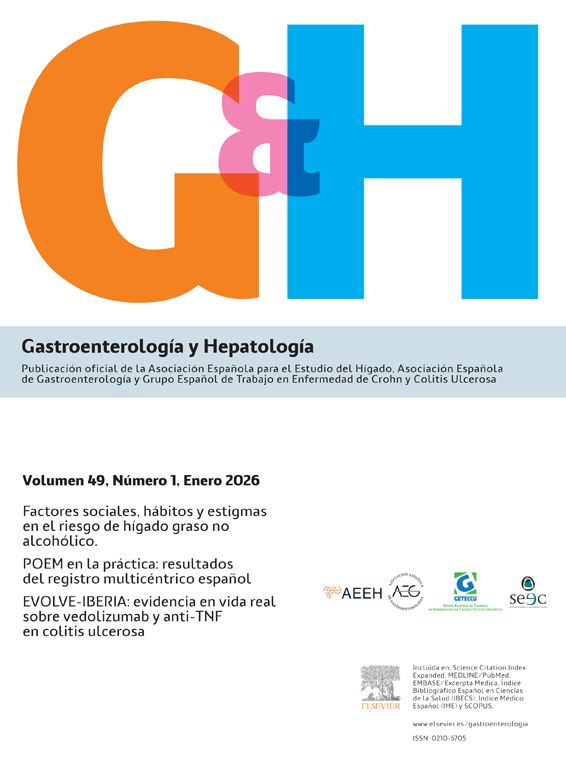

En el examen radiológico del abdomen, se apreciaban asas del intestino delgado dilatadas (fig. 1), al igual que en la ecografía abdominal, en la que las asas fueron descritas como hipoactivas y con contenido en su interior. Se practicó un transito barritado que mostró una estenosis en el segmento medio del intestino delgado, con paso filiforme del contraste (flechas de la fig. 2).